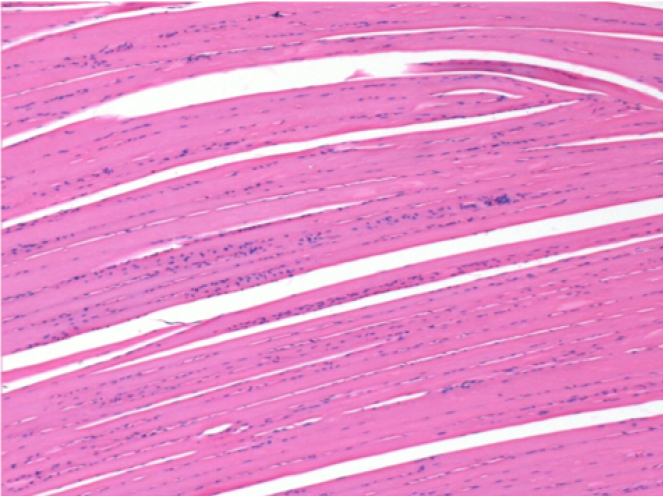

3 months (D90)after Endopeel Injection 0.1ml in the right pretibial muscle.